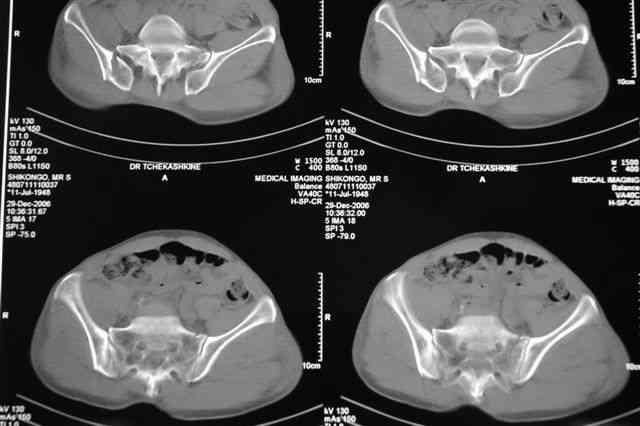

Я помню технику транссакральной фиксации тазового кольца длинными 5 мм Шанцами - повреждения типа В, в этом же случае задний отдел тоже вовлечен

т.е комбинированная нестабильность, поэтому вопрос - достаточно ли только двух Шанцев для стабилизации таза? Что вы думаете об anterior Right SI joint plating + tension band plating from the back.?

Элегантная фиксация, поздравляю.Но ваш случай : одноплоскостная горизонтальная нестабильность Tyle B2.2 отличен от представленного мной - у

моего больного + вертикальная нестабильность за счет повреждения правого крестцово-подвздошного сочленения и перелома заднего отдела подвздошной

кости- С2 тип. Поэтому и возникла дилемма : выбор оптимальной фиксации заднего отдела:

По-поводу фиксации таза спонгиозными винтами. Данный способ все-таки показан для фиксации повреждения крестцово-подвздошного сочленения или переломов крестца. Мне кажется, что в данной случае ситуация иная - имеется перелом "основания" крыла подвздошной кости (в который вовлечена и поверхность, составляющая крестцово-подвздошное сочленение). Не уверен, что фиксация данного повреждения (и заднего полукольца) винтами будет стабильной, так как именно на уровне 1-2 крестцовых позвонков (где обычно вводят винты) линия перелома уходит в латеральном направлении от крестцово-подвздошного сочленения.

PI>По-поводу фиксации таза спонгиозными винтами. Данный способ все-таки показан

для фиксации повреждения крестцово-подвздошного сочленения или переломов крестца. Мне кажется, что в данной случае ситуация иная - имеется перелом

"основания" крыла подвздошной кости (в который вовлечена и поверхность, составляющая крестцово-подвздошное сочленение). Не уверен, что фиксация данного повреждения (и заднего полукольца) винтами будет стабильной, так как

именно на уровне 1-2 крестцовых позвонков (где обычно вводят винты) линия перелома уходит в

латеральном направлении от крестцово-подвздошного сочленения.